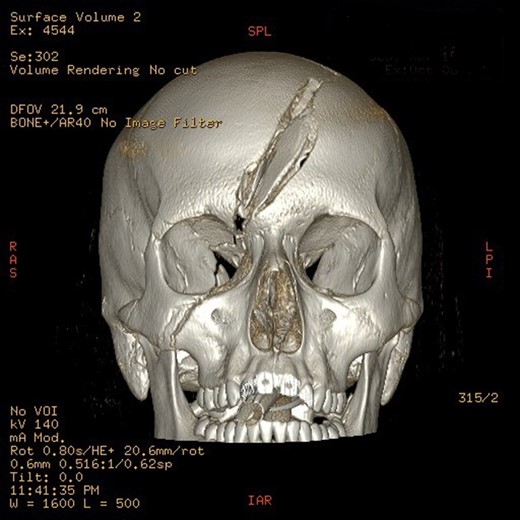

Mr AB is a 16-year-old male multi-trauma patient secondary to a high speed motor vehicle accident. His injuries included a frontal open comminuted depressed skull fracture with a fragment displaced and abutting the superior sagittal sinus (Fig. 1). The fracture line involved the right medial orbital wall extending through the ethmoid air cells and roof of the right sphenoid sinus (Fig. 2). Other cranial injuries included a fracture through the right side of the greater wing of the sphenoid bone, frontal intraparenchymal contusions and a traumatic subarachnoid/subdural haematoma. He had a laceration extending across the left side of his forehead to the medial canthus. His extracranial injuries included proptosis of his right eye, a closed unstable pelvic fracture with involvement of the left superior gluteal artery and a subcapsular liver haematoma.